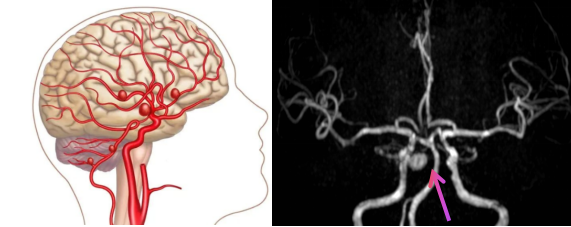

你可能听说过“颅内动脉瘤”,虽然名字里带“瘤”,但它和我们常说的“肿瘤”完全不同。它其实是脑内血管壁上一个异常鼓起的“包”,就像一根长期使用的老旧水管,在某处突然鼓起一个薄弱点。一旦血压突然升高,这个位置就可能破裂,就像水管爆裂一样危险!

颅内动脉瘤最大的风险,就是破裂导致脑出血,这是神经外科中最危急的情况之一。可怕的是,它在破裂之前,绝大多数人根本感觉不到任何症状。因此,如果能提前发现并处理,就能极大降低生命危险,改善康复效果。

磁共振血管成像(简称MRA)就是一种安全、无创又可靠的筛查方式。它不使用放射线,也没有创伤,被称作“绿色检查”。其中,无对比剂增强MRA(3D-TOF技术)尤其受欢迎——不需要注射造影剂,也没有辐射风险,就能立体、多角度地展示脑内血管的形态,就像给脑血管拍了一张“三维全景照片”。

这种技术能清晰呈现脑动脉主干及3-4级分支,对颅内动脉瘤的诊断能力非常强。据统计,其检测敏感度高达约95%,特异度约89%。也就是说,它不仅“找得准”,还能“辨得明”。对于直径大于2mm的动脉瘤,诊断准确率更可达98%以上。此外,MRA还能帮助发现血管狭窄、闭塞、先天发育异常或血管畸形等问题。